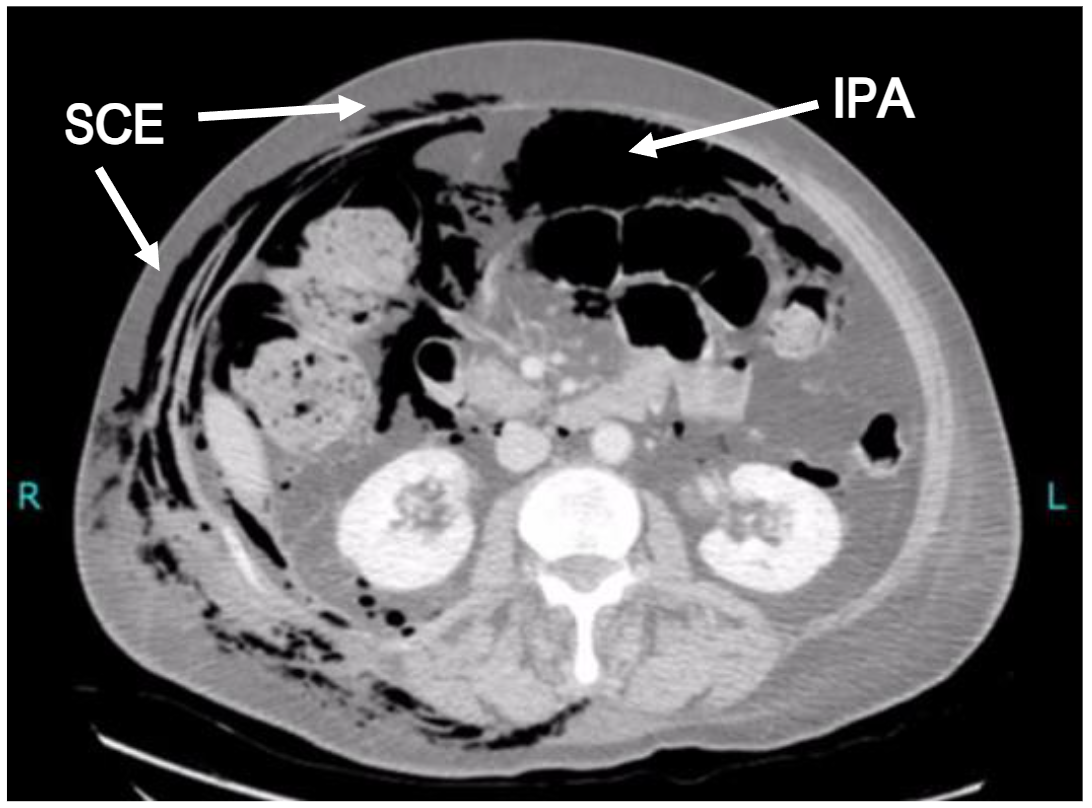

However, computed tomography (CT) is becoming a much more common early diagnostic tool as the rapidity, yield and specificity of radiological information is significantly greater. In the case of subcutaneous emphysema, CT imaging may reveal its anatomical site and extent, it may still be extremely challenging for the reporting radiologist to identify its origin in the absence of relevant clinical information or intra-abdominal stigmata. Indeed, subcutaneous emphysema of the head, neck and thorax may not even prompt the clinician to request inclusion of the abdomen. Occasionally, however, the information provided by an adequate CT scan is invaluable and can lead to a rapid diagnosis (see Figure 2). This review aims to encourage clinicians to include sub-diaphragmatic causes of acute subcutaneous emphysema within their differential diagnosis.